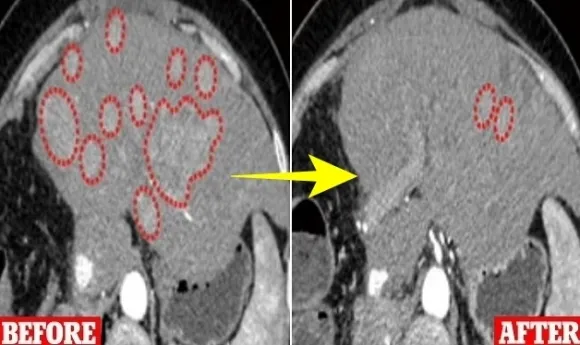

연구진은 간암 세포를 가진 원숭이 10마리를 대상으로 실험을 진행했다. 위약을 받은 원숭이 5마리는 모두 4개월 이내에 죽었지만, 변형 바이러스 치료를 받은 원숭이는 6개월 이상 생존했다.

연구진은 또 간, 식도, 직장, 난소, 폐, 유방, 피부, 자궁경부 등 여러 암 진단을 받은 환자 23명을 대상으로 같은 변형 바이러스를 이용해 실험했다. 환자 중 1명을 제외한 모든 사람은 8~12주 동안 일주일에 한 번씩 변형 바이러스를 주사했다.

2년 후 피실험자 23명 중 2명의 암 세포는 줄어들었지만 완전히 사라지지는 않았다. 5명의 암세포는 성장을 멈췄고, 1명은 암세포가 성장을 멈췄다가 다시 커지는 결과를 보였다. 피실험자 중 어떤 긍정적인 효과도 보이지 못한 사람은 2명이었고, 또 다른 2명은 실험 시작 약 1년 만에 실험을 포기했다.